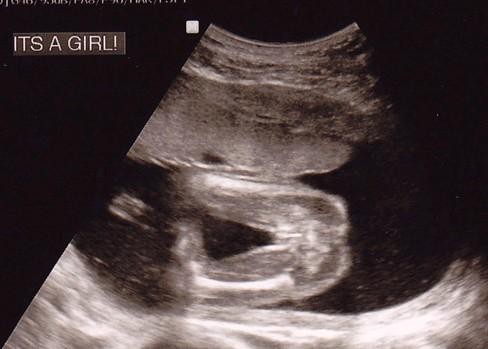

进行邮寄验血测胎儿性别需满足一定条件。一般来说,孕期需达到6周以上,且胚芽长度达3mm以上,以确保血液中胎儿的DNA含量足够用于检测。